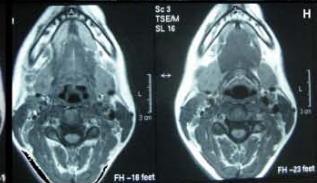

Figure/Patient 3

An 8 year-old girl with prior surgical excision of a right latero-cervical lymphangioma presenting with a new-onset tumefaction within the same region. MRI scans show a 9-10 cm subcutaneous multilocular lesion, extending between two virtual planes crossing the retro-molar trigone and the thyroid respectively, with deep invasion of parapharyngeal spaces cranially and the space between the submandibular gland and the vascular peduncle of the neck caudally. The lesion appears hyper-intense on T2 weighted scans with (A-B) and without (C-D) fat suppression, hypo-intense on T1 weighted scans with (E) and without (F) fat suppression and hyper-intense on DWI scans with high B values (G). Diagnosis of loco-regional recurrence of cystic lymphangioma is done.